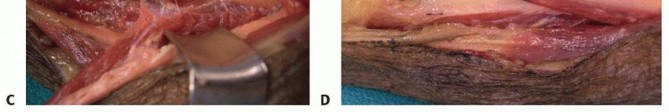

A longitudinal incision is made along the radial border of the mid-forearm. The superficial fascia is divided, and the interval between the brachioradialis (BR) and the flexor carpi radialis (FCR) is developed. The superficial radial nerve (SRN) and radial artery are identified and carefully retracted. The broad, flat insertion of the PT onto the lateral aspect of the radius is visualized.

Image

To maximize the length of the donor tendon, a strip of periosteum (approximately 1.5 to 2 cm) is harvested in continuity with the PT insertion from the radius. This periosteal extension is crucial, as the PT tendon itself is quite short. Once detached, the PT is mobilized proximally. Care must be taken not to dissect too aggressively on the deep surface of the proximal PT, as this risks injury to its median nerve motor branches.

Next, the ECRB and ECRL tendons are identified dorsally. The ECRB is located slightly more ulnar and deep to the ECRL. The PT tendon is routed subcutaneously over the BR to reach the ECRB. The routing must be superficial to the BR to avoid compression of the transfer during muscle contraction.